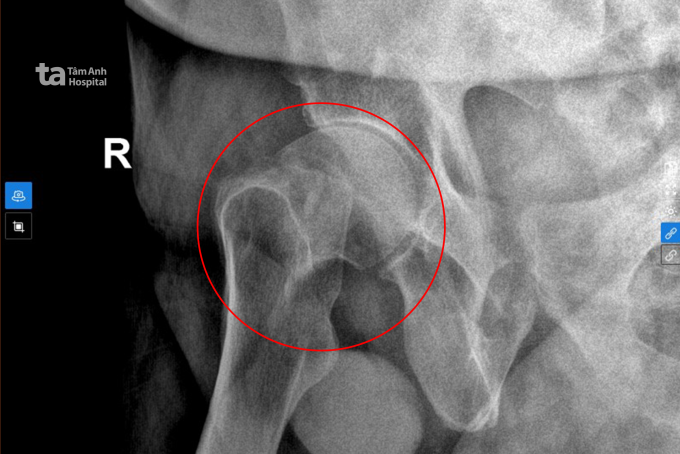

Ông Paul, 69 tuổi, gãy xương đùi, được bác sĩ thay khớp háng trong chưa đầy 24 giờ nên sớm đi lại bình thường. Ông Paul, quốc tịch New Zealand, ngã, đến Bệnh viện Đa...